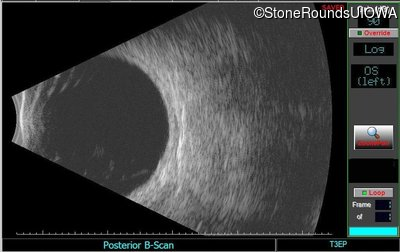

B-Scan Ultrasonography - Left - 20/500 sc

Exemplar